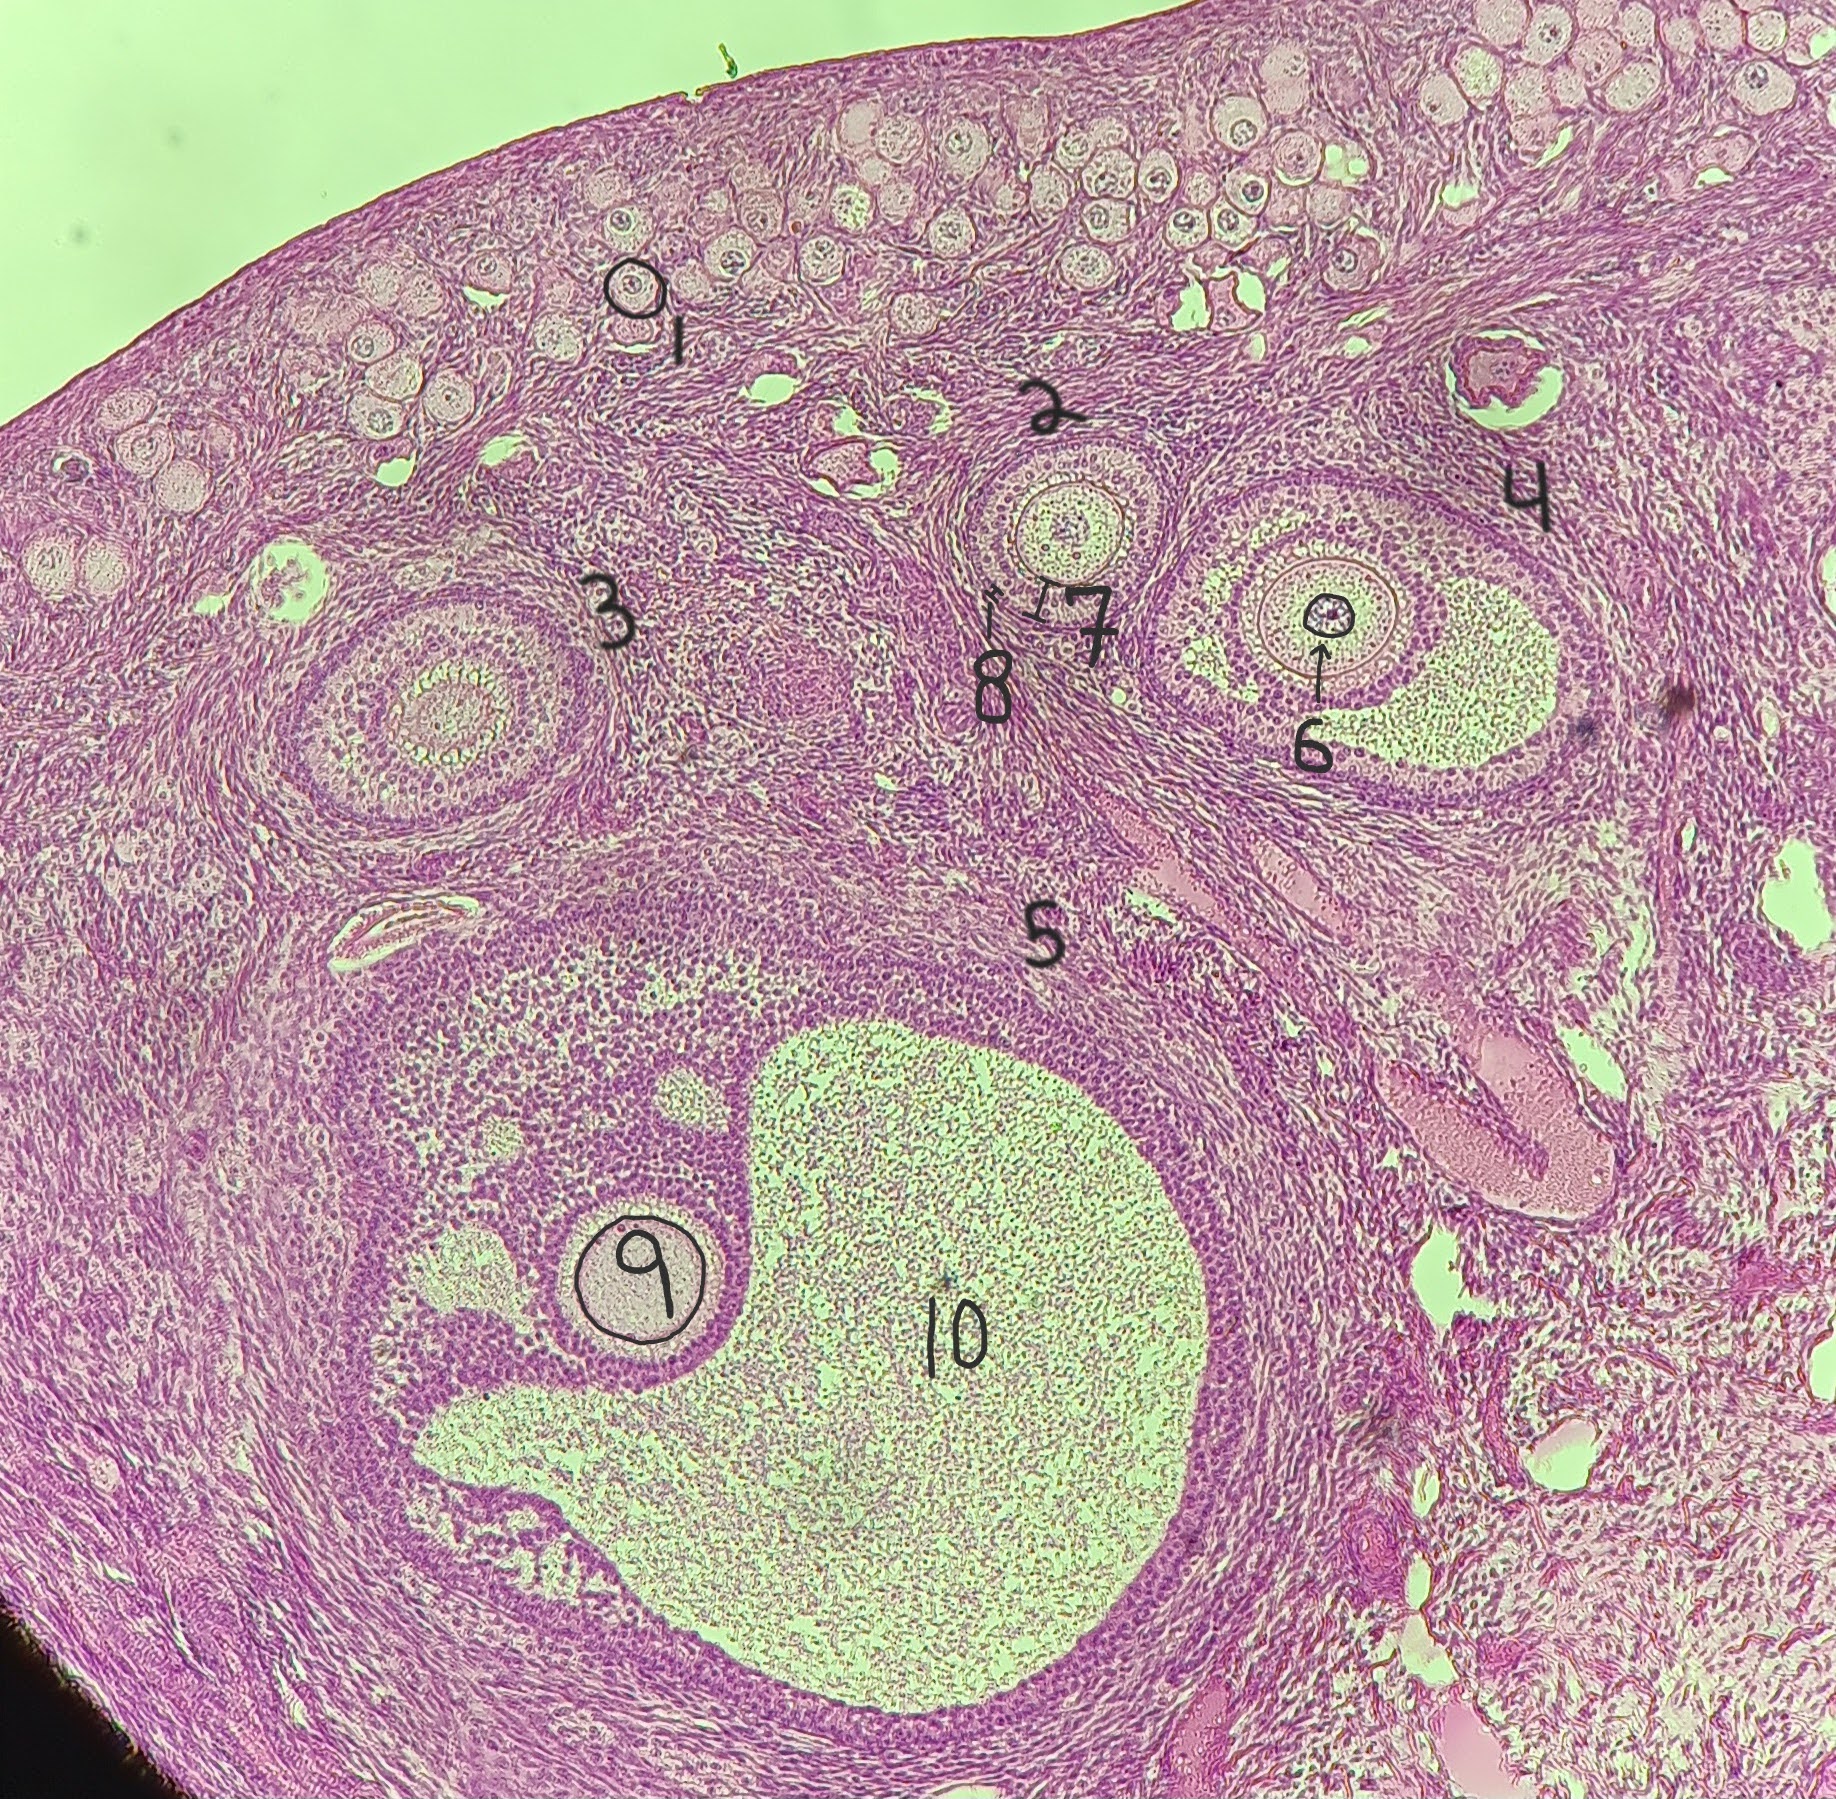

Primordial follicle

1

Primordial follicle

Primordial follicle

1

Primary follicle

2

Primary follicle

Primary follicle

2

Secondary follicle

3

Secondary follicle

Secondary follicle

3

Tertiary follicle

4

Tertiary follicle

4

Mature follicle

5

Mature follicle

Mature follicle

7

Antrum

10

Zona pellucida

9

Theca folliculi

8